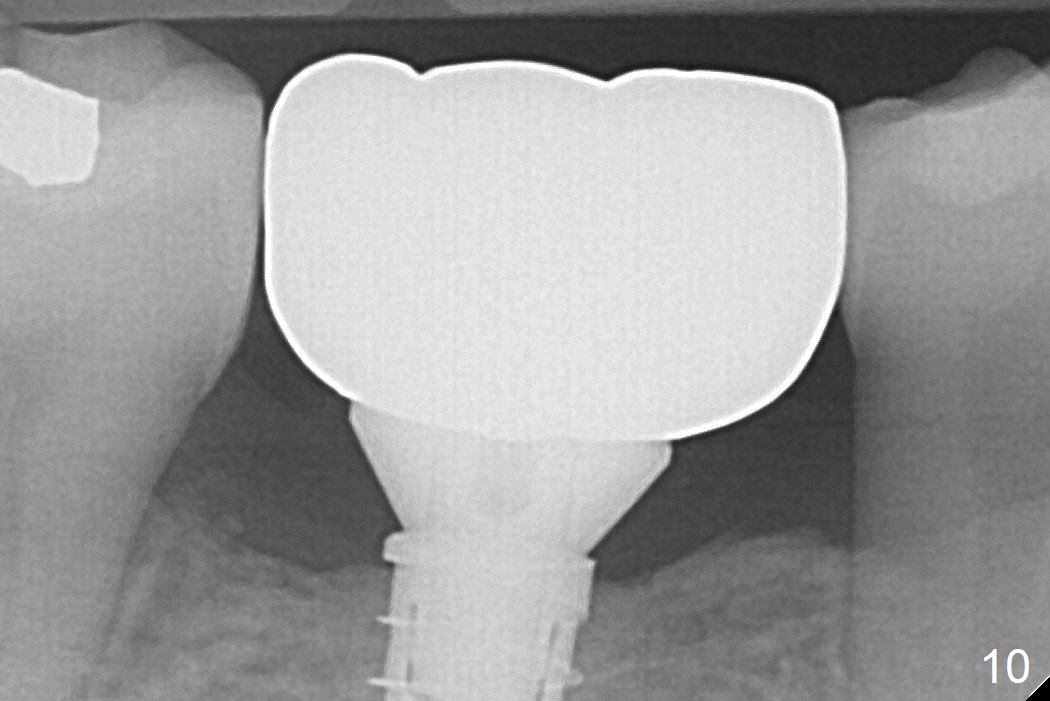

A provisional is fabricated 1 month postop to prevent the tooth #31 from rotation under the tension of the open coil spring, as mentioned above. Acrylic is added distal for #31 distalization nearly 2 months postop. More definitive orthodontic action begins 3 months postop (Fig.7, banding and open coil spring). The edentulous space increases to satisfactory width 3.5 months postop (Fig.8). A normal sized crown is delivered 4 months postop (Fig.9). The patient is pleased with the new tooth (Fig.10 nearly 6 months post cementation). There is no bone loss 13 months post cementation (Fig.11 (pan), 12 (CT coronal section (L: lingual))).